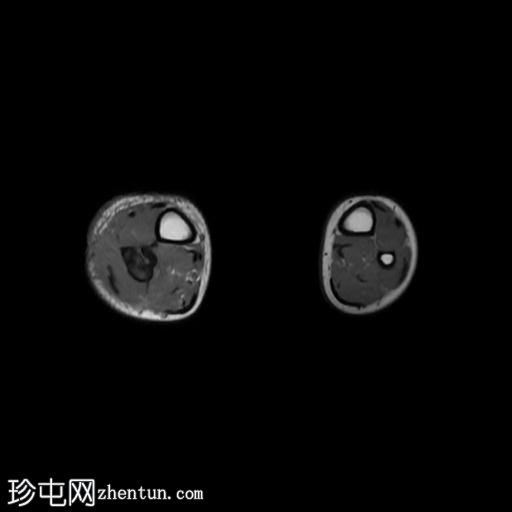

MRI

轴位

T1加权像